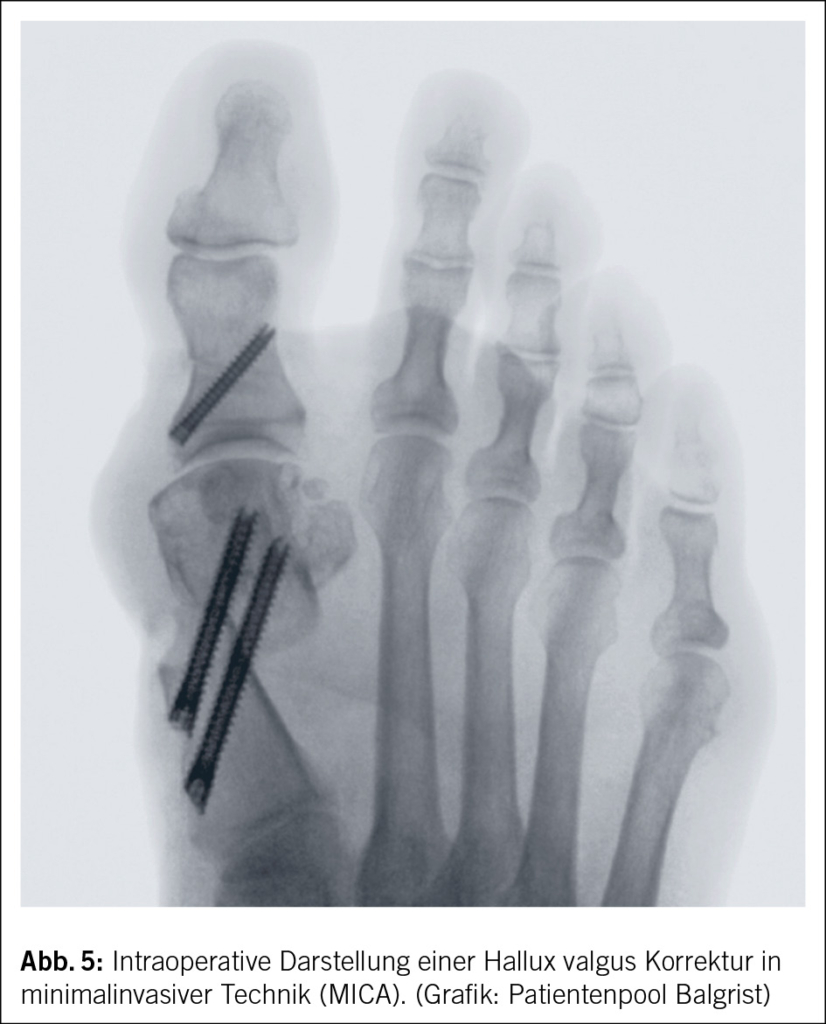

Aktuell im Trend sind auch minimalinvasive Hallux valgus Operationen, auch MICA genannt (Minimal Invasive Chevron and Akin osteotomy) (Abb. 5). Die aktuell nun dritte Generation, mit Schraubenfixierung befestigte Variante osteotomiert das Metatarsale über diverse kleinere Schritte und fixiert es anschliessen mit grosskalibrigen langen Schrauben (28, 29). Die MICA konnte sich gegenüber den herkömmlichen Verfahren allerdings noch nicht als besser beweisen, so können mit der MICA Versorgung jedoch gewisse Indikationen erweitert werden, die bislang mit einer Versteifung versorgt wurden.

MICA Minimalinvasive Chevron und Akin Osteotomie